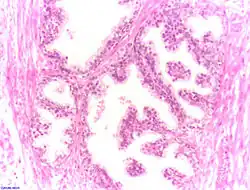

- Histologische Schnitte

-

Normales Prostatagewebe

Normales Prostatagewebe -

Noduläre Hyperplasie

Noduläre Hyperplasie

Die feingewebliche Untersuchung (Histologie) von Prostatagewebe gehört nicht zur regulären Diagnostik einer BPH. Bei Bedarf erfolgt sie entweder aus einem Operationspräparat oder aus einer zum Ausschluss eines Prostatakrebses gewonnenen Gewebeprobe. Bei der BPH finden sich keine malignen Zellen, dagegen weist das Gewebe im Vergleich zur gesunden Prostata einen knotigen Umbau durch die Proliferation von Stroma und Drüsenepithel auf. Typisch sind wirbelförmige Muskelknoten und mit einem einschichtigen Epithel ausgekleidete, herdförmige Drüsengänge. Diese knotigen Veränderungen sind meist relativ groß und daher in kleinvolumigen Gewebeproben nicht erkennbar. Die Variationsbreite der Veränderungen ist weit, bei der BPH findet sich aber immer ein einschichtiges Epithel, dagegen fehlen Zellatypien.[23][24]